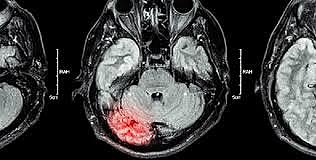

Griesinger (1817 a 1868): Planeaba que se podía establecer una relación directa entre los diferentes trastornos psicopatológicos y lesiones anatómicas en el sistema nervioso central.